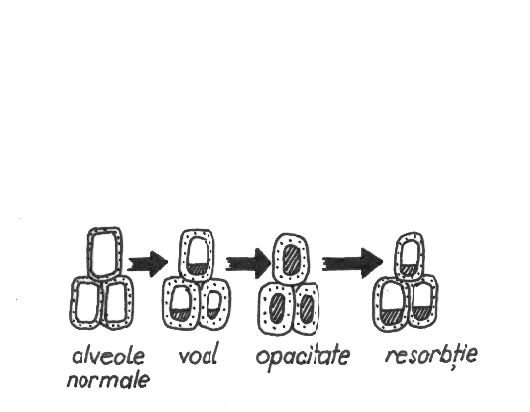

Radiodiagnosticul pneumopatiilor acute

Radiodiagnosticul pneumopatiilor acute In functie de stadiul de evolutie, modificarile radiologice vor fi oglinda celor morfopatologice. Faze de evolutie: Faza de congestie alveolara - peretii alveolariCiteste tot ... 447 cuvinte

Dimensiune mica

+ cu imagini |